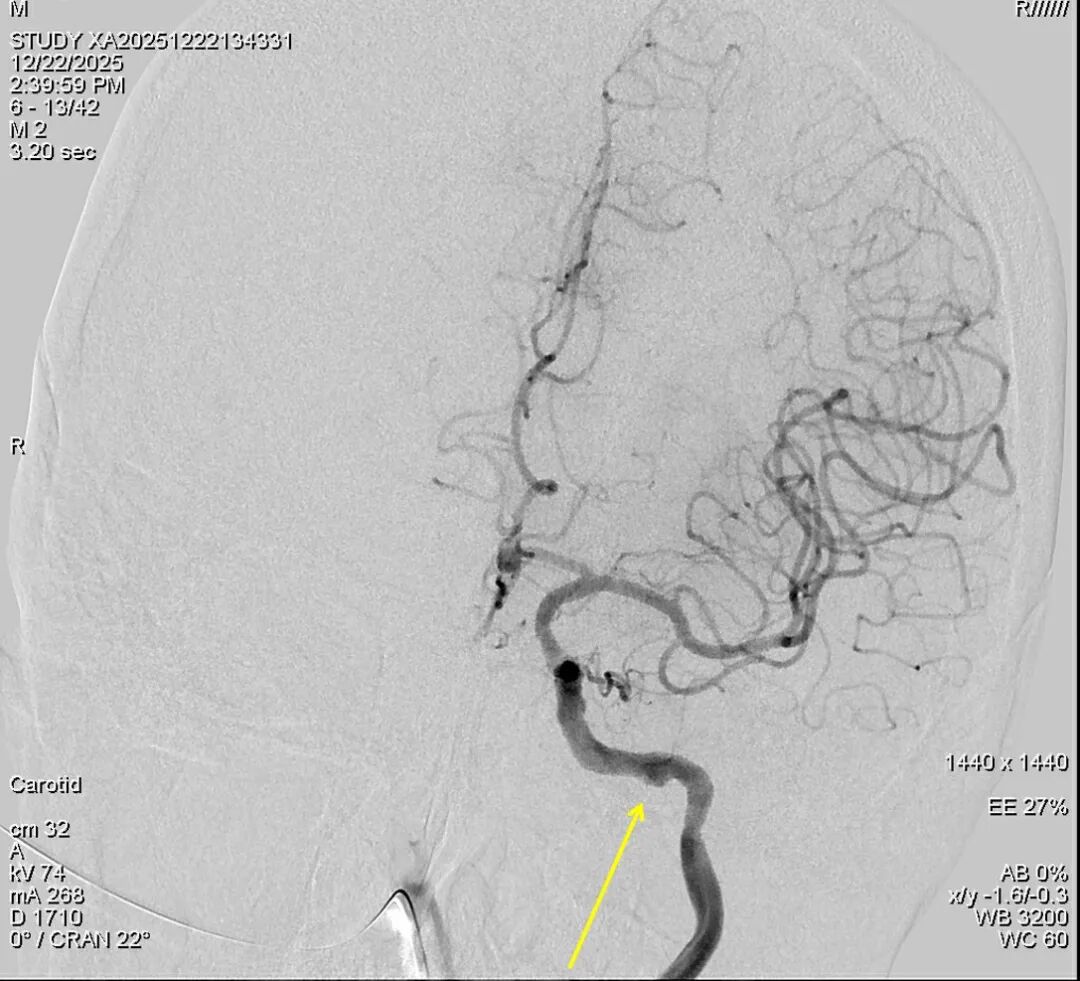

面对如此棘手的局面,颅底外科中心组织了全院病例讨论,耳鼻咽喉头颈外科、颅底外科、神经外科、血管外科、影像科、肿瘤科等各专业术20多位主任医师进行了紧急讨论。佟小光院长带领的血管外科团队果断决策,患者颈内动脉长程受到破坏接受开颅高流量搭桥手术应是最优选择,但是患者身体状态差而且经前期抢救后心理状态差惧怕搭桥手术,可以选择局麻微创血管内介入治疗,这样能为患者赢得宝贵的时间获得二期病变切除和颅底修复的机会。经过充分准备,环湖医院王红光副院长和复合脑血管外科尚彦国主任联手为患者在局麻状态进行了左侧颈内动脉破裂处第二枚覆膜支架的植入,将破裂点彻底封堵,同时在右侧重度狭窄的颈内动脉植入了扩张支架,这样既避免了再次出血的风险也保证了患者颅内的供血,为后续根治手术创造了至关重要的前提条件。

术前DSA:右侧颈内动脉起始段重度狭窄,左侧颈内动脉岩骨段假性动脉瘤形成

术后DSA:右侧颈内动脉支架后通畅,左侧颈内动脉岩骨段覆膜支架后假性动脉瘤消失